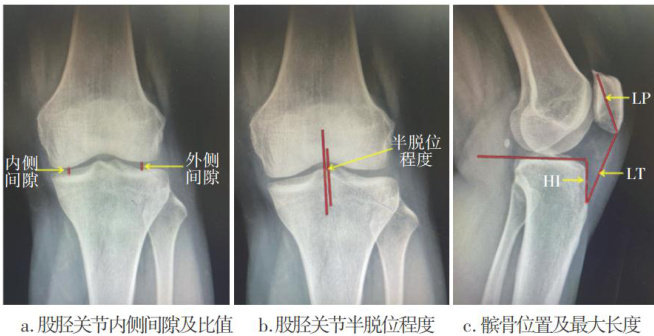

膝骨关节炎足阳明经筋病变与X线影像学测量指标的关系